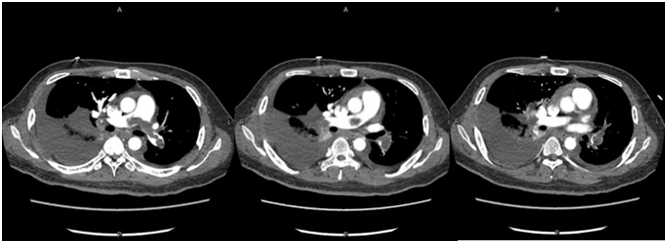

根据临床表现、影像学及肺栓塞临床评分,诊断急性肺血栓栓塞症(中高危组)明确。进一步排查深静脉血栓栓塞的易感因素,其父有肝癌病史,需进一步排查肿瘤因素,同时完善血栓调节组合、抗凝治疗监测组合等相关检查,以了解是否存在先天性抗凝因子缺乏。鉴于患者有溶栓指征,无明显溶栓禁忌证,将溶栓风险告知患者及家属,其理解并同意溶栓治疗,于2017年6月15日16:00予阿替普酶50 mg静脉持续泵入2 h溶栓治疗,溶栓时及溶栓后密切监测凝血功能变化。此外,结合患者胸部CT提示肺部有渗出,血白细胞升高,有发热、明显咳嗽、咳痰症状,考虑社区获得性肺炎(非重症),有使用抗生素指征,结合社区感染相关病原体,予左氧氟沙星0.5 g ivdrip qd经验性抗感染治疗。经上述治疗,患者仍有气促,间断咳嗽,咳少量血丝痰,2017年6月17日腹部彩超提示:①双侧少量胸腔积液;②肝静脉,汇入下腔静脉低回声,血栓形成可能;③肝、胆、脾、胰、肾、输尿管、膀胱、前列腺均未见异常。复查其凝血功能未达标,加用华法林抗凝治疗,初始剂量3 mg po qn,考虑药物需3~5 d才能达到稳定的血药浓度,为达到快速抗凝目的,使INR达到2~3,继续予低分子肝素0.8 ml H q12h重叠抗凝。同时为了解华法林量效关系,予完善CYP2C9和VK0RC1检查,通过基因多态性检测,有助于指导华法林初始剂量的选择。抗凝治疗期间多次复查凝血功能,根据结果调整抗凝药物剂量。溶栓后5 d,患者仍诉气促,呕吐频繁,反复低热,热峰不超过38℃,复查床边胸部X线片提示右侧大量胸腔积液(图2),行超声引导下胸腔穿刺置管引流术;查肝功能示转氨酶升高,予护肝治疗;加强抗感染(亚胺培南西司他丁1.0 g ivdrip q8h)。患者症状无明显好转。2017年6月20日开始频繁诉恶心呕吐,吐出胃内容物,发热,气促,活动后加重,咳嗽,咳血丝痰,无明显胸痛或胸闷不适,右侧胸腔引流管引流出血性液体。查体:神清,双上肺及左下肺呼吸音清,右下肺呼吸音明显减弱,未闻及干/湿啰音,心率111次/min,各瓣膜区未闻及病理性杂音。腹部平坦,肝右肋缘下5 cm可触及,质软,无触痛。复查出、凝血常规示:D-二聚体25.07 mg/L FEU,INR 3.19,APTT 49.7 s;ESR 56 mm/h;胸腔积液检查结果提示渗出液。取胸腔积液标本找肿瘤细胞。复查心脏彩超:下腔静脉肝后段至右心房实性回声,考虑血栓形成,估测肺动脉压28 mmHg(图3)。考虑恶心呕吐与肝静脉血栓形成、肝淤血致肝功能异常相关,停用可能导致肝损害的药物,继续抗凝,加强护肝、退黄、平喘治疗及营养支持。经上述治疗,患者气促情况有好转,但肝功能损害加重,肝酶、胆红素及血氨水平进行性升高,凝血功能明显异常,ALT 1819 U/L,AST 6345 U/L,LDH 5860 U/L,TBIL 70.8 μmol/L,DBIL 27.6 μmol/L,IBIL 43.2 μmol/L,维持护肝、降血氨治疗,及时纠正非预期凝血功能障碍,复查胸+上腹+下腹CTA平扫+增强+三维,查风湿组合Ⅰ+Ⅱ,自身免疫性肝病组合,抗磷脂综合征组合等相关检查,帮助明确肺血栓情况,查找肝功能进行性异常的原因,风湿免疫相关检查结果无异常。2017年6月22日行CTA示:①肺动脉主干,左、右肺动脉干,左上、下肺动脉及其分支,右下肺动脉主干及外基底段近段肺动脉栓塞,左下肺动脉栓塞较前范围稍扩大,右下肺动脉病变范围较前稍减轻;下腔静脉近右心房至肝段上部、下腔静脉肾静脉水平—双侧髂总静脉—双侧髂外静脉及肝左、中、右静脉管腔多发血栓形成,较前进展。②肺部炎症、胸腔积液。③心包积液较前稍增多,腹腔、盆腔少量积液(图4)。注:A:右心房血栓;B:下腔静脉延续到右心房处血栓,肝静脉未显影;C:CTA示下腔静脉近右心房端、肝静脉多发血栓形成;D:CTA另一层面示下腔静脉血栓,肝内静脉未显影,考虑栓塞;E、F:复查胸部CTA示肺动脉主干栓塞6月22日夜间患者出现谵妄、躁动不安,不能正确应答,查血氨升至191 mmol/L(图5)。考虑患者多部位静脉血栓形成,肝静脉栓塞,肝脏淤血明显,已并发肝性脑病,有急性肝衰竭可能,予乳果糖口服溶液灌肠,门冬氨酸鸟氨酸降血氨治疗,患者解出大便后症状稍好转,密切观察肝功能变化情况。请院内多学科会诊,多学科意见考虑患者目前存在多部位静脉血栓,急性肝损伤,凝血功能严重异常,手术风险极大,不建议行手术取栓治疗,建议继续内科药物治疗,可考虑行二次系统溶栓。与患者及家属沟通病情并取得知情同意后,2017年6月25日行第二次溶栓,予阿替普酶50 mg静脉持续泵入2 h,同时密切观察全身出血情况,预防出血,继续对症支持治疗。患者意识障碍加重,尿少,出现肝肾综合征,凝血功能异常。床边腹部超声:①右肝静脉血栓形成、闭塞,中肝静脉第二肝门处血栓形成,血流通畅,双向血流;②下腔静脉血栓形成,彩色多普勒血流成像(CDFI)探查不佳;③左肝静脉双向血流;④肝动脉、门静脉血流通畅。当天患者意识障碍进一步加重,昏迷状,呼吸衰竭,行气管插管接呼吸机辅助通气,气道内吸出血性分泌物,多次复查结果示肝功能及凝血功能严重异常,低纤维蛋白原血症,考虑存在肝静脉、下腔静脉血栓相关的布加综合征。请血液科会诊,考虑低纤维蛋白原血症系由肝损、溶栓药物、DIC消耗等多因素引起,建议完善凝血因子监测,根据结果及INR补充新鲜冰冻血浆、凝血酶原复合物、维生素K1等。患者因少尿,行床边连续性肾脏替代治疗(CRRT),体外肝素化抗凝,但因滤器及管路凝血而提前结束治疗。请感染科会诊,建议继续予护肝、降酶、退黄治疗,补充血浆及白蛋白,加强肺部及腹部抗感染治疗。请血管外科会诊协助处理肝静脉血栓,血管外科建议考虑下腔静脉、肝静脉机械取栓或置管溶栓,辅以全身肝素化抗凝,以改善肝脏血流,但因手术风险极高,家属不愿行取栓/溶栓术。虽给予积极药物治疗,患者肝功能改善情况不理想,凝血功能差,反复输注血制品情况下出现顽固性低纤维蛋白原血症,合并全身散在部位出血,预后差,2017年6月30日家属办理自动出院手续。| 该患者入院时无明显血流动力学不稳表现,影像学显示双肺动脉栓塞较严重,存在肺动脉骑跨,发病早期即发现肝静脉、下腔静脉多发血栓形成,入院后1周内出现肝衰竭,病程进展迅速。针对该患者的治疗难点有哪些?回顾这一病例,是否有更有效的方法进行治疗? |